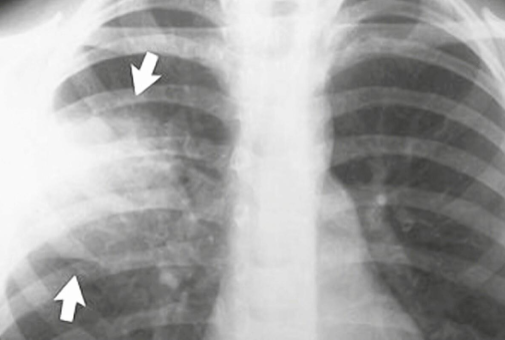

زمانی که شما نفس میکشید، هوا وارد ریه ها و کیسه های هوایی میشود. اگر میکروبی وارد ریه شد و به بر سیستم ایمنی بدن غلبه کرد، کیسه های هوایی دچار عفونت و ورم شده و منجر به بیماری سینه پهلو میشود. سینه پهلو می تواند باعث علایم و نشانه هایی مانند تب، سرد شدن بدن، سخت نفس کشیدن توام با درد، خستگی یا سرفه شود.

- باکتری معمولی ذات الریه – چندین نوع باکتری می توانند باعث ذات الرّیه شوند. ولی از همه قوی تر استرپتوکوکوس نومونیّا (Streptococcus pneumonia) میباشد. این نوع نومونیّا معمولا بعد از سرماخوردگی یا فولو(Flu) اتفاق می افتد.